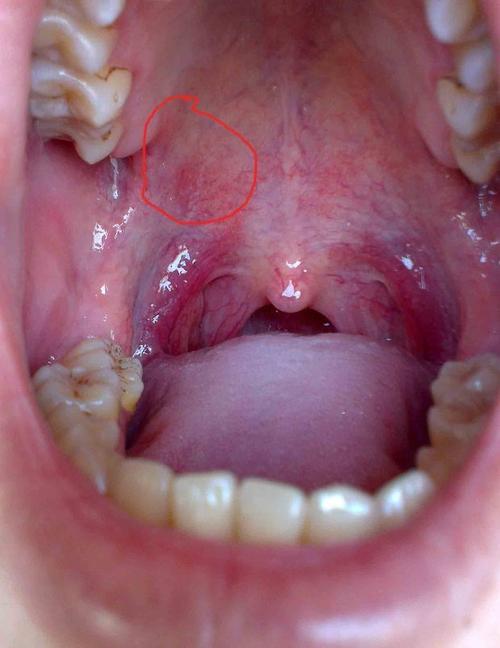

口腔上颚凸起压痛是何问题?

下面我们来分析一下口腔上颚凸起压痛的可能原因,从最常见到相对少见的情况: